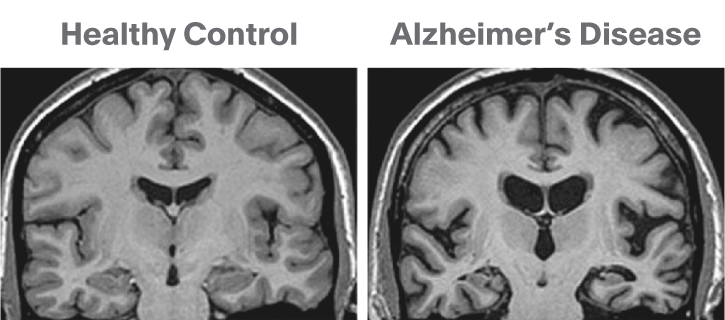

A Shrinking Brain

The brain experiences some shrinking with normal aging and significantly more in age-related diseases. With Alzheimer’s, a significant amount of shrinkage occurs because of damage and resulting degeneration from the disease. Alzheimer’s actively attacks brain cells, impairing their function and eventually leading to cell death.

BrightFocus Alzheimer’s Disease Research grantee, Dr. Zahra Shirzadi, is identifying imaging patterns for injury to the white parts of the brain (shown above) and evaluating their use for predicting Alzheimer’s risk. Learn more.